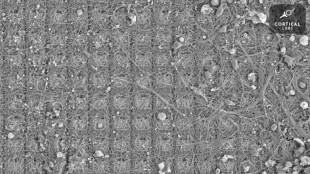

Des neurones doués de sensations ont appris à jouer à un jeu vidéo (étude)

Des neurones cultivés dans une boîte de Petri sont capables d'apprendre à jouer à Pong, le grand classique des jeux vidéo, faisant ainsi preuve d'un "comportement intelligent et doué de sensations", selon des chercheurs en neurosciences australiens.